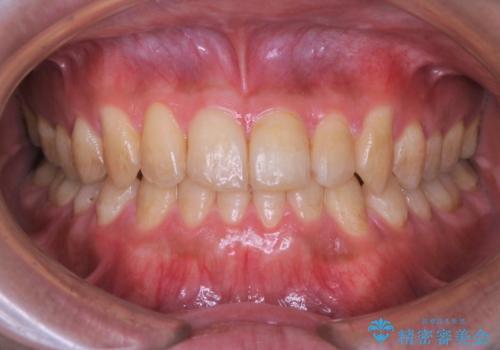

矯正治療を終えてのクリーニング

担当医 歯科衛生士